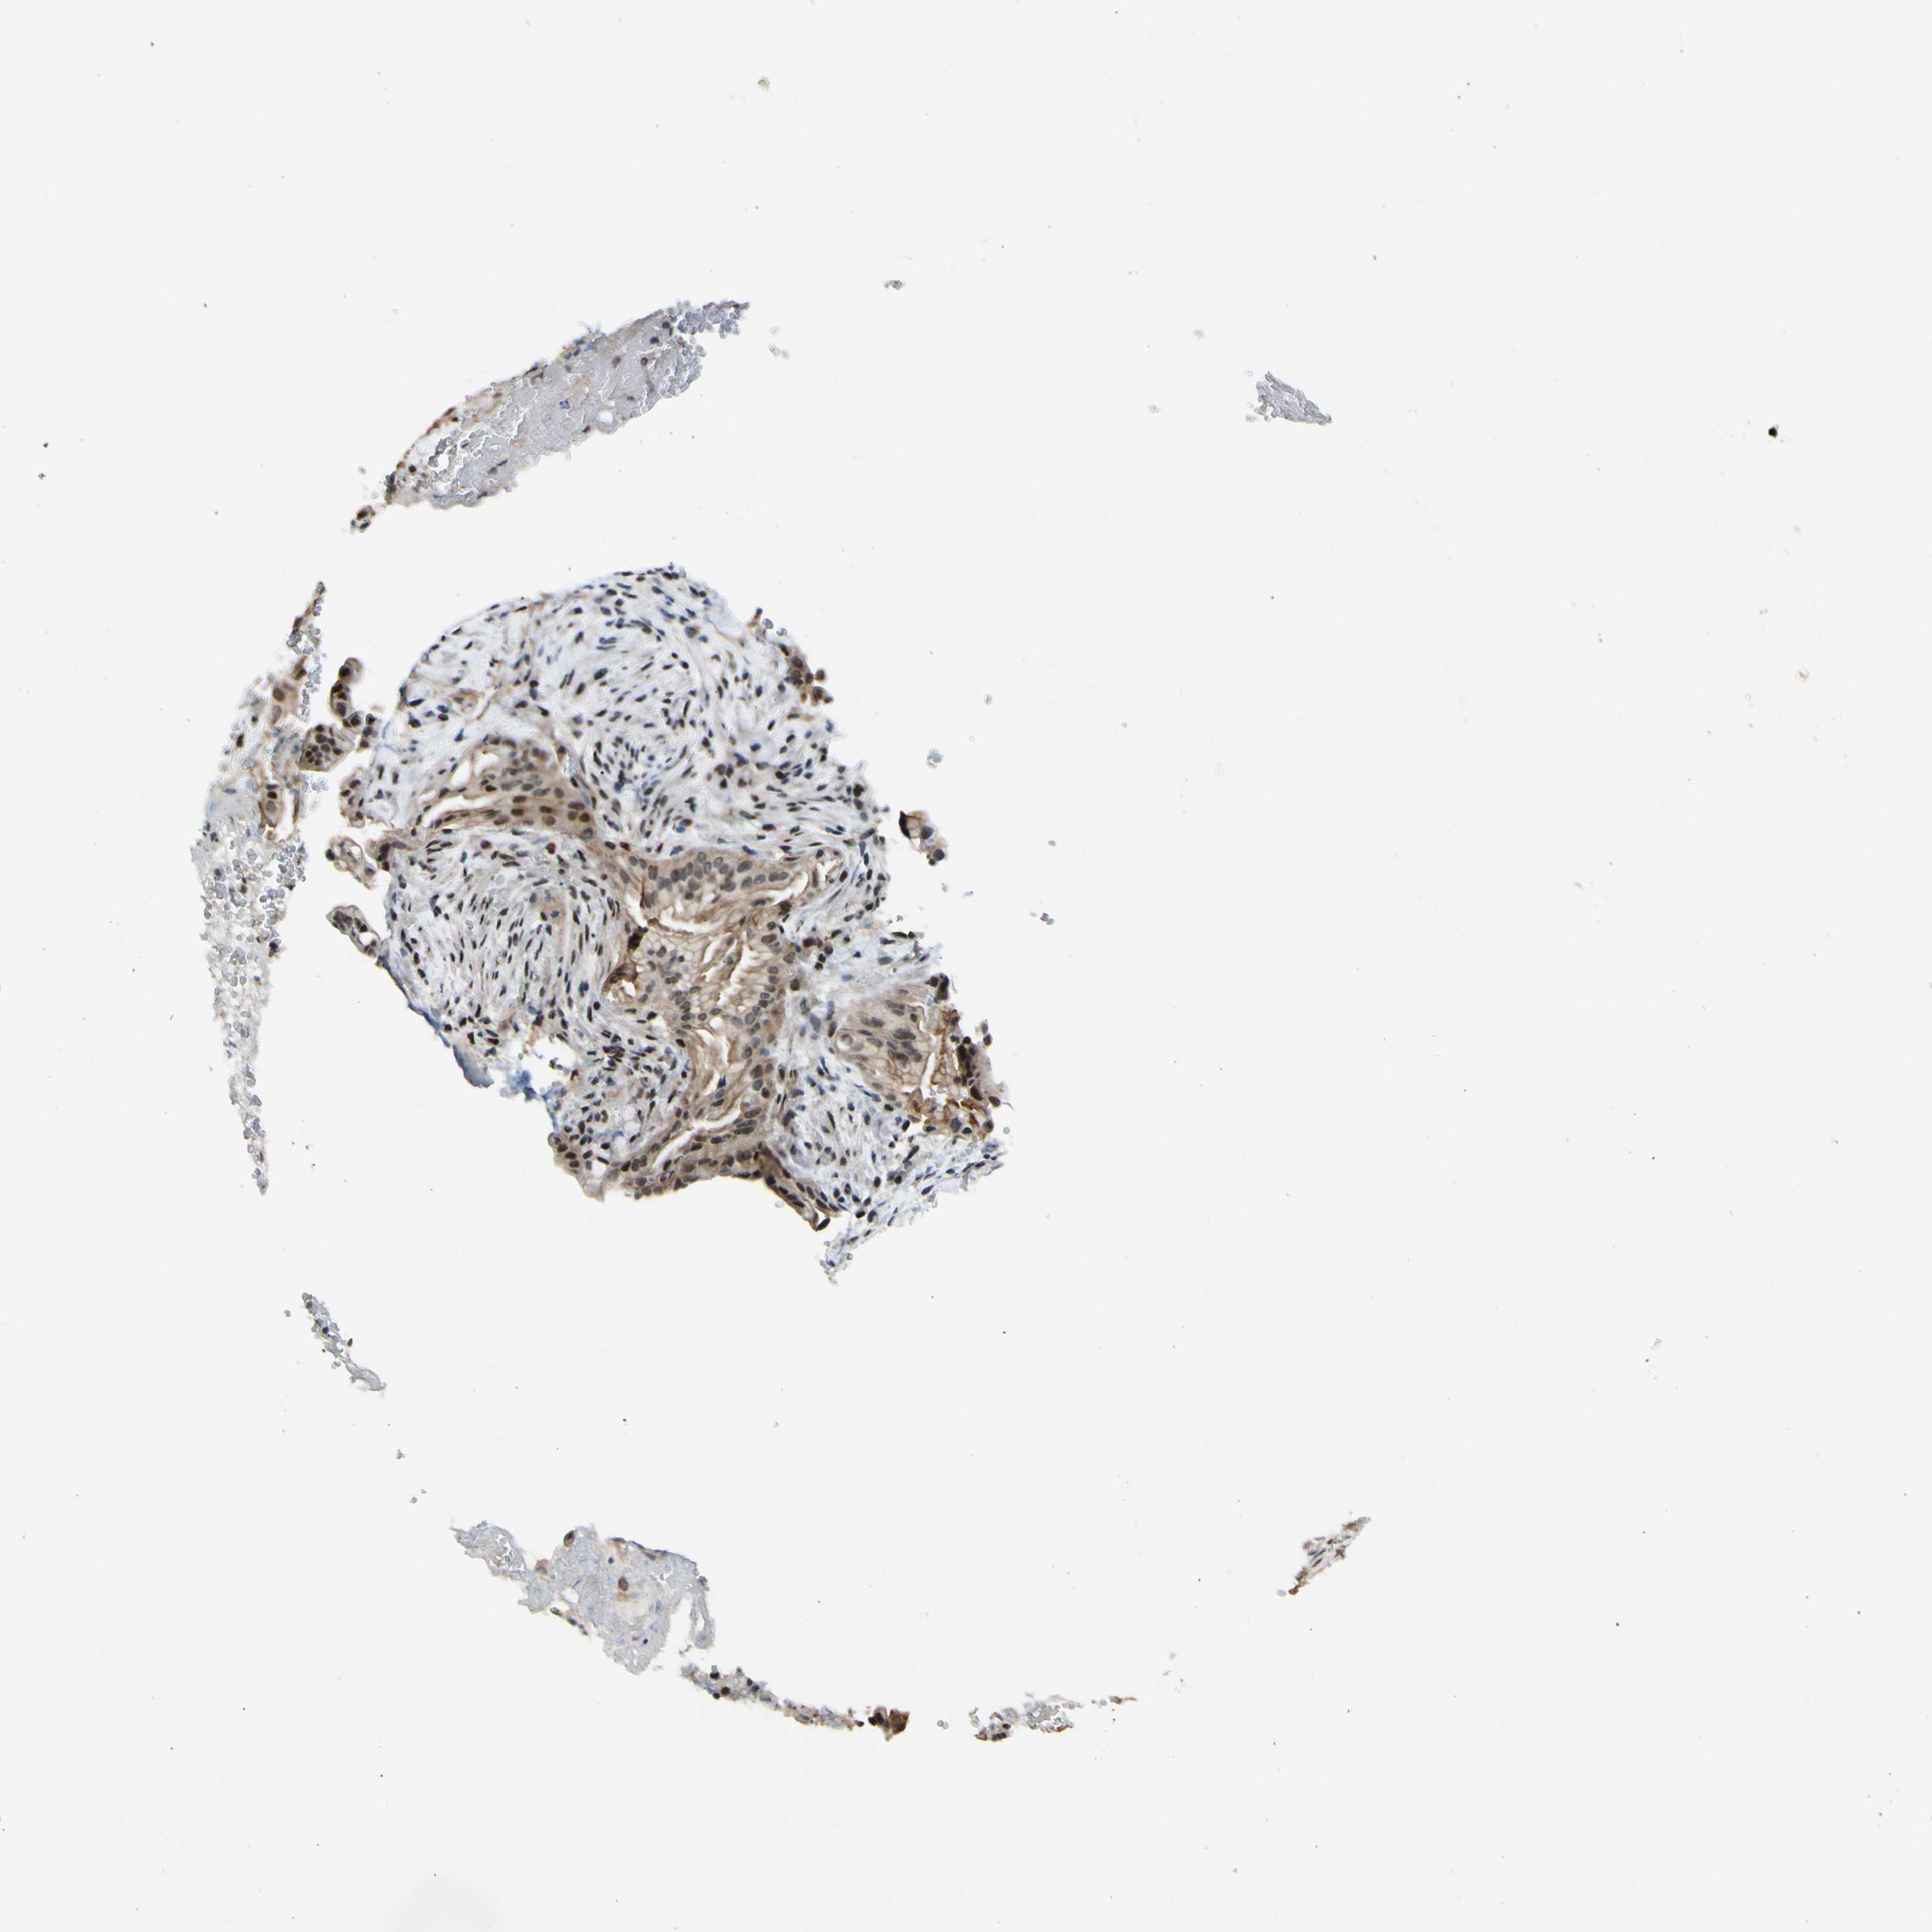

LIVER CANCER - Protein expressioni

A mouse-over function shows sample information and annotation data. Click on an image to view it in a full screen mode. Samples can be filtered based on level of antibody staining by selecting one or several of the following categories: high, medium, low and not detected. The assay and annotation is described here.

Note that samples used for immunohistochemistry by the Human Protein Atlas do not correspond to samples in the TCGA dataset.

Antibody stainingi

Antibody staining in the annotated cell types in the current human tissue is reported as not detected, low, medium, or high, based on conventional immunohistochemistry profiling in selected tissues. This score is based on the combination of the staining intensity and fraction of stained cells.

Each image is clickable and will lead to virtual microscopy that enables deeper exploration of all samples and also displays staining intensity scores, fraction scores and subcellular localization as well as patient and tissue information for each sample.

Antibody HPA008700

Staining

High

Medium

Low

Not detected

Intensity

Strong

Moderate

Weak

Negative

Quantity

>75%

75%-25%

<25%

None

Location

Nuclear

Cytoplasmic/membranous

Cytoplasmic/membranous,nuclear

Cholangiocarcinoma

Carcinoma, Hepatocellular, NOS